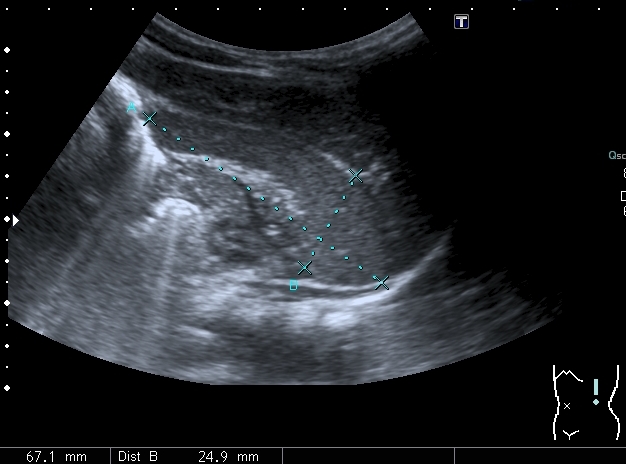

Ребёнок 2.5 месяцев, доставлен в связи с выявленным при очередном осмотре увеличением печени.

При УЗИ: печень резко увеличена, больше за счёт левой доли

Паренхима печени -гиперэхогенная , неоднородная, практически полностью замещена нодулярными образованиями, некоторые из них с "гало" и кальцификацией

Правый надпочечник представлен округлым гиперэхогенным тканевым образованием с участками кальцификации, гиповаскулярным по отношению к ткани печени и почки